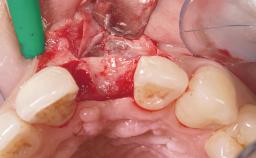

A 29-year-old female patient presented for treatment to replace the upper left central incisor tooth with an implant- supported restoration. The tooth had been intermittently symptomatic for the previous 12 months. The tooth had originally suffered trauma about 15 years previously. Several endodontic treatments had been performed, including an apicectomy procedure to retain the tooth. The patient was healthy and a non-smoker. She had reasonable expectations in regard to esthetic outcomes and the risk of marginal tissue recession following treatment. At medium smile, the gingival margins of the upper teeth were visible, with a display of 3 to 4 mm of the gingival margins. Gingival recession of tooth 21 and a discrepancy in the gingival levels between teeth 11 and 21 was observable during normal speech and smile.

| Soft Tissue Grafting | None |

| Placement Protocol | Immediate implant placement |